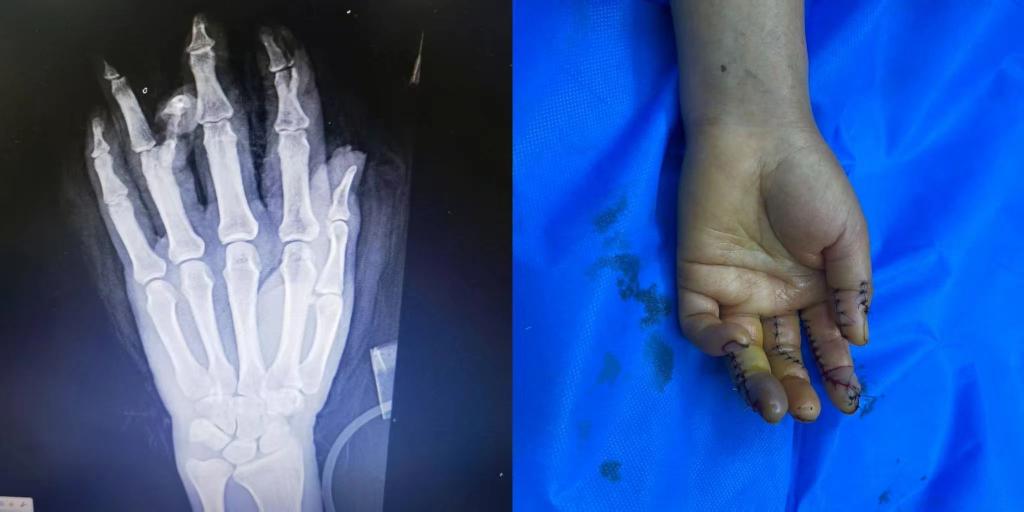

5月1日下午15点30分,beat365唯一官方网站第五临床医学院2020级临床医学班的学生小马(化名)接到了来自伊犁亲戚的电话。电话中得知,亲戚在工作中不幸遭遇意外,左手被机器压伤,导致拇指、食指、中指、无名指均受到不同程度的损伤,受伤最严重的是食指和无名指,竖向劈开了骨头。由于多指多段离断的严重毁损伤,手术难度很大,当地医院的条件有限,为保住患者手指,需要申请前往上级医疗机构治疗。

随后,患者被送入手术室,由李华医生主刀,进行了长达7个小时的断指再植手术。

术后患者损伤严重的手恢复了基本形态,手指末梢血液循环逐步恢复。目前患者的情况基本平稳,在医院等待进一步观察和恢复。